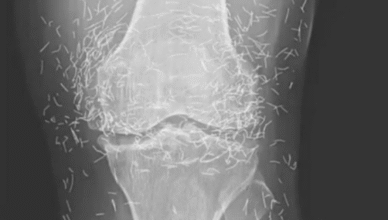

Czy każdego ranka budzisz się z uporczywym uczuciem zmęczenia i bólu stawów, który ogranicza Twoją swobodę ruchu? Może szukasz naturalnego rozwiązania, które pozwoli